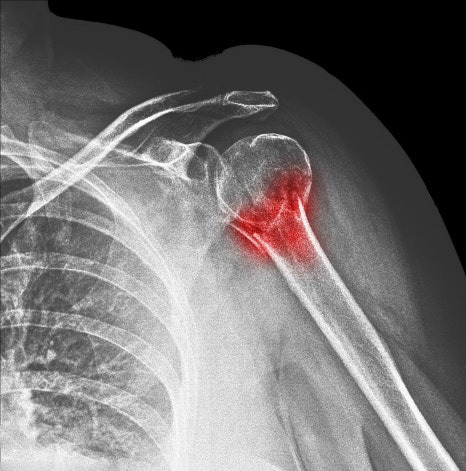

석회성건염이란? - 어깨 힘줄에 쌓이는 석회

석회성건염은 어깨 관절을 움직이는 힘줄 특히 회전근개 힘줄 내부에 칼슘 성분이 침착되면서 염증 반응과 통증을 동반하는 상태를 말합니다. 겉으로 보기에는 뼈나 관절에 큰 이상이 없어 보여도 힘줄 안쪽에서 변화가 생기면서 불편감이 시작되는 것이 특징입니다.

이 질환은 넘어지거나 부딪힌 기억 같은 뚜렷한 외상이 없어도 발생할 수 있고 일상생활에서 반복되는 사용 습관이나 어깨 힘줄의 회복 환경이 좋지 않은 상태가 누적되면서 서서히 진행되는 경우가 많습니다.